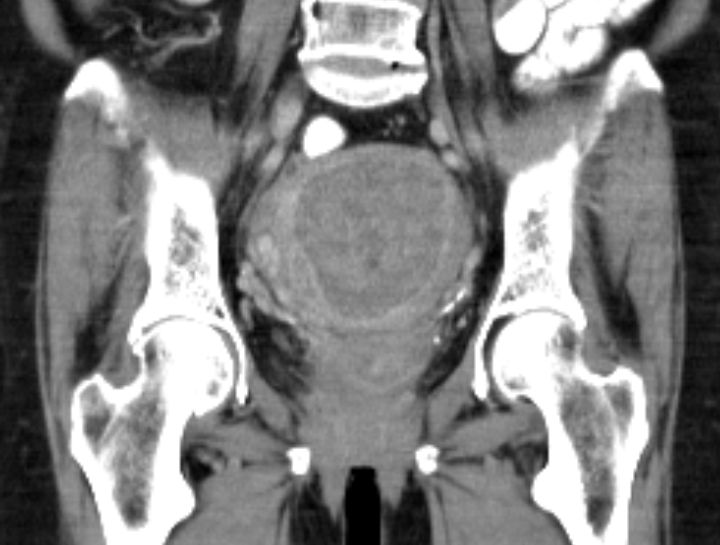

69-jährige Frau, die vor 4 Jahren ein Mammakarzinom hatte und adjuvant mit Anastrozol behandelt wird.

Wegen PM-Blutung wurde eine Abrasio durchgeführt, die einen malignen Müllerschen Mischtumor des Endometriums ergab.![]() |

Postoperatives Stadium pT1a (beginnende Wandinfiltration) pNo Mo Lo Vo Ro![]() | |